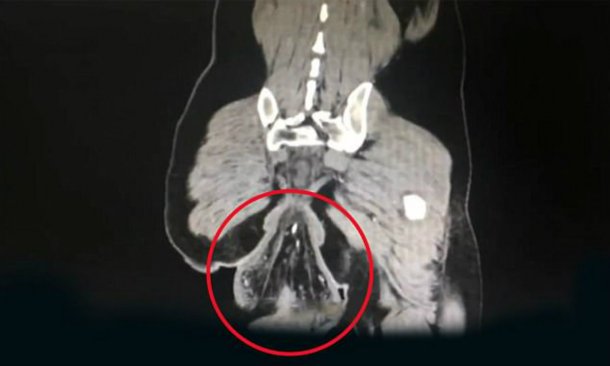

O caso ocorreu na China, em Zhongshan. Um homem sofreu um “prolapso retal”, que é quando há um extravasamento do intestino, ou seja, o reto se separa do abdômen e deixa o corpo. O homem teve que ser levado para a emergência.

A médica que realizou o procedimento, Su Dan, disse: “O paciente já tem prolapso retal desde os quatro anos, mas nunca tratou da questão e durante esses últimos tempos seu estado de saúde piorou”.

Depois de passar horas sentado no banheiro, mexendo no celular e fazendo força, seu ânus acabou cedendo e descolou-se. O caso é realmente sério e foi importante que o homem tenha sido levado às pressas para o hospital.

O homem, cuja identidade não foi informada para preservar a sua identidade, foi internado no hospital da Universidade de Sun Yat-sen em 4 de fevereiro, e está em fase de recuperação depois de ter sido operado, conforme informou o site KanKanNews.